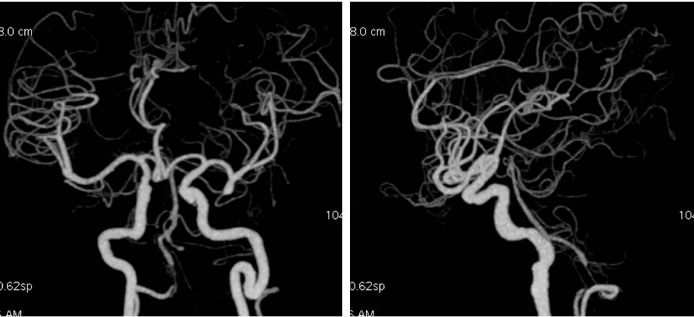

患者,男,46岁,主因“头晕3个月,眩晕伴恶心呕吐2个月”入院。患者3个月前突发头晕,伴头部昏沉感,持续时间短,程度轻,初未予重视。2个月前出现眩晕,伴恶心呕吐,就诊当地医院,行头颅MRI:左侧小脑小灶梗死,右椎动脉V4段狭窄,基底动脉远段显影欠佳,左椎动脉V4未见显影(图1,2)。

外院DSA:右椎动脉V4段次全闭塞,基底动脉有顺向显影,前向血流减慢;左椎动脉V3段闭塞,见基底动脉经脊髓前动脉代偿显影(图3,4)。